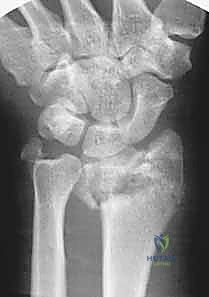

كسور عظم الكعبرة البعيد، خاصة تلك الناتجة عن حوادث قوية أو سقوط من ارتفاعات عالية، تمثل تحديًا طبيًا وجراحيًا كبيرًا. هذه الكسور تختلف تمامًا عن كسور الرسغ البسيطة التي قد تحدث نتيجة تعثر بسيط. في حالات الطاقة العالية، غالبًا ما تتسبب القوة الميكانيكية الهائلة في تهشم العظم وتفتته إلى قطع صغيرة (Comminution)، وتؤثر بشكل مباشر ومدمر على سطح المفصل الحساس (Intra-articular fractures).

الميكانيكا الحيوية للإصابة (Biomechanics of Injury)

في حوادث الطاقة العالية (مثل حوادث الدراجات النارية أو السقوط من السقالات)، يتم دفع عظام اليد بقوة هائلة داخل عظم الكعبرة، مما يؤدي إلى "انفجار" العظم من الداخل وتفتته (Pilon-type fractures). هذا التفتت يجعل العظم غير قادر على تحمل أي ضغط، وينهار على نفسه (Collapse).

- الأشعة السينية (X-rays): بأوضاع متعددة لتقييم زوايا الكسر ومقدار الانهيار العظمي.

- الأشعة المقطعية (CT Scan) مع إعادة البناء ثلاثي الأبعاد (3D Reconstruction): وهي خطوة إلزامية في الكسور المعقدة. تتيح للدكتور هطيف رؤية كل شظية عظمية داخل المفصل بدقة متناهية والتخطيط للعملية الجراحية قبل دخول غرفة العمليات.